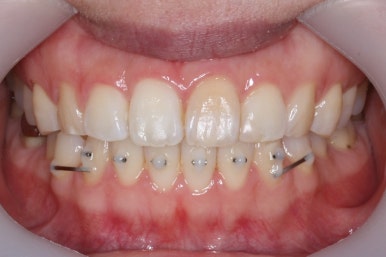

세 번째 조절입니다.

가지런한 정도는 매우 좋아졌고, 군데군데 틈새가 있어서 조여주고 있는 상황입니다.

이정도만 되어도 결혼식을 진행하시기에 어느 정도 만족도 있는 수준까지 왔다고 생각되어졌습니다.